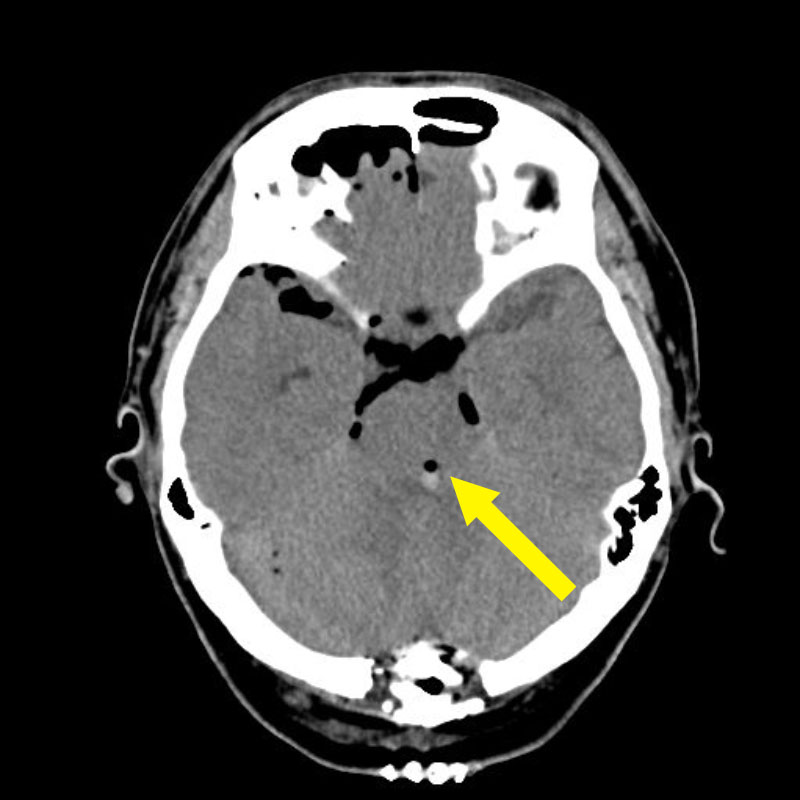

'25年1月

50代

南田,野本

右小脳

出血性海綿状血管腫

再出血の予防目的

兵庫県の病院

より紹介

No.No.59 手術前1

No.No.59 手術前2

No.No.59 手術後1

No.No.59 手術後2

CT/MRにより完全に摘出されたことが確認された